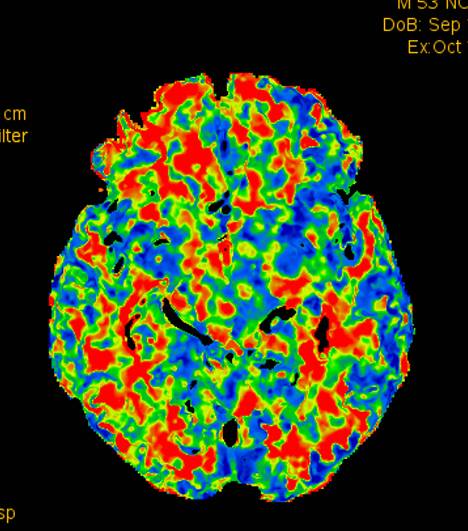

术前CTP示:右侧大脑半球灌注较差。

术后2个月患者未再诉右眼黑曚。复查CTP示:颅内灌注明显改善。

术前灌注成像,右侧大脑半球灌注较差。